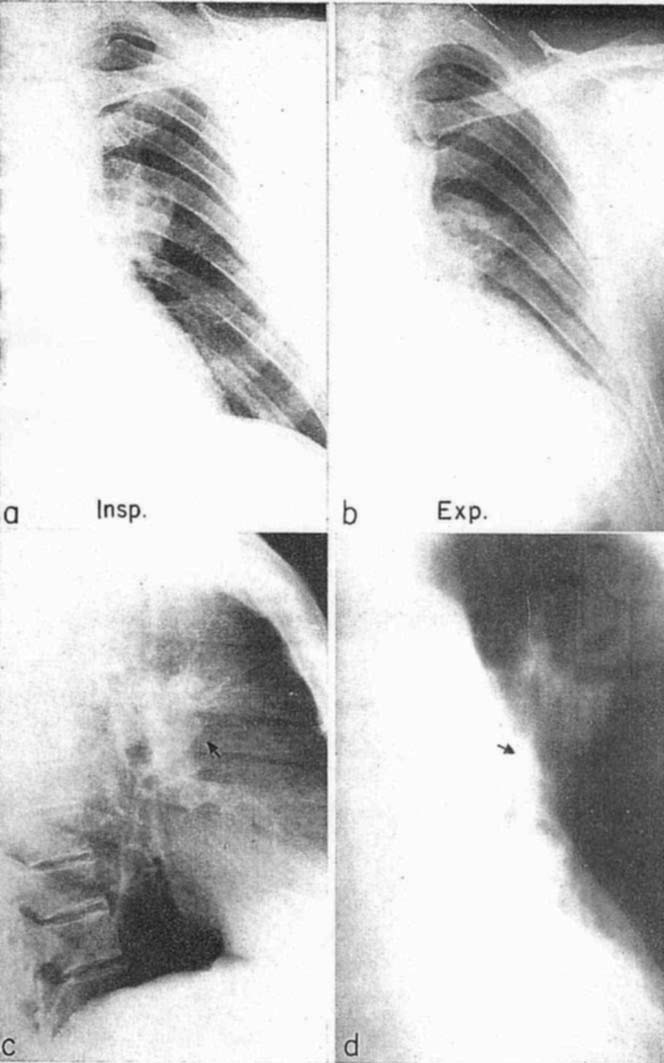

図6.1923年のSanteによる大葉性肺炎のX線所見に関する報告は,肺炎のX線診断の基礎を確立した.左下葉の肺炎の経時的変化[].

最も一般的な胸部疾患である肺炎のX線所見については初期から多くの記載がある.1910年代までは,X線装置など技術的な条件が不備であったため,肺炎を頻回,経時的に観察して比較することが難しかった.1923年にSanteは大葉性肺炎のX線所見とその経時的変化に関する系統的な研究を行ない,大葉性肺炎では数日単位で均一な濃厚陰影が出現,次第に不均一な陰影となる過程を示し,また胸膜炎,膿瘍などの合併症にも言及して肺炎診断の基礎を確立した[→原著論文](図6).1927年には肺炎の重要なX線所見のひとつである air bronchograms がFleischnerによって記載されている[→原著論文].無症状でX線写真によってのみ診断できる肺炎の存在が知られるようになる一方で[14],肺炎のX線所見は非特異的で,多くの場合X線による起炎菌診断が難しいことも明らかとなった.

図10. 肺葉別の硬化像の見え方.

【要旨】過去2年にわたって経験した大葉性肺炎272例中152例について,それぞれ複数回のX線撮影を行ない,臨床所見と対比した.大葉性肺炎のX線所見は一葉ないし複数葉に限局性する均一な硬化像(consolidation)で,肺門部に始まって通常24~48時間で辺縁部まで及び,臨床的なクリーゼから5~7日で消退するのが原則である(図10).14日以上陰影が持続する場合は合併症を疑う.合併症には,完成胸膜炎,胸水,形成性漿液線維素性胸膜炎,慢性間質性肺炎,肺膿瘍などがある.梅毒性肺炎,結核性肺炎との鑑別には臨床所見が重要である.大葉性肺炎と胸水の鑑別は難しいが,X線管球を高位において撮影することにより鑑別できる.

【解説】この時期になるとようやく技術的な条件が整い,X線透視だけでなくX線撮影をルチーン検査として行えるようになった.供覧されている写真の画質は現在の水準から見ても遜色ないもので,十分な診断能を備えたものといえる.大葉性肺炎のX線所見,経時変化,合併症,特に胸水との鑑別について,自らの経験をもとに詳細に記載されており,その内容は現在の教科書の記述と大きな違いはない.やや奇異に思えるのは,大葉性肺炎が中枢に初発して末梢に及ぶか,あるいはその逆かという点についてかなりの字数が費やされていることであるが,この背景には当時,聴打診で診断が難しい肺門部に優位な「中枢性肺炎」(central pneumonia)という病態が議論されていたことがある.著者の結論は肺門部に初発して末梢に及ぶことが多いというものであるが,大葉性肺炎の病態から言うと逆であろう.

図11. 左図.肺梗塞.右下肺野の陰影内に,明るい線条陰影(気管支の透亮像)が認められる.右図.葉間胸水.右下肺野の陰影内には暗い線条陰影(血管陰影)が認められる.

【要旨・解説】肺実質性病変を示唆する基本的なレントゲンサインとして知られるair bronchograms の初報である.著者は,肺野の均一な陰影内の明るい線条構造に気づき,その樹状構造から気管支と考えた(図11).このよう濃厚陰影内の気管支透亮像は,肺炎,肺梗塞など肺実質病変で認められ,胸膜病変(胸水)では認められない.胸膜病変,特に葉間胸水の貯溜でみられる陰影は肺病変との鑑別を要することがあるが,この所見があれば鑑別しうると結論している.

図13. 左肺門部肺癌.(a)正面像で肺門腫大があり,(b)呼気撮影で左上葉に閉塞性肺気腫が認められる.(c)側面像,(d)断層撮影で肺門部腫瘤が認められる.

【要旨・解説】1954年に開催された第55回米国レントゲン学会(ARRS)年次総会における「肺癌シンポジウム」(Symposium on Carcinoma of the Lung)の一連の講演のひとつで,肺癌のX線所見,X線検査の診断的意義に関する総論である.このシンポジウムは肺癌のレントゲン診断をテーマとしており,この他に肺癌の病理所見とレントゲン所見の相関(Liebow AA),X線透視による肺癌スクリーニング(Garland LH),肺癌の外科的診断(Davis EWら)が論じられている.本稿はこれらの中にあって,主に単純X線写真の所見について述べ,必要に応じて断層撮影,気管支造影が有用であるとしている.肺癌を示唆する所見として,次の11項目を挙げている.

(9) 呼気撮影における限局性気腫像 (図13)

(10) 中高年者に突然発症した無気肺

(11) 気管支内腔の異常(断層撮影,気管支造影)

これらはいずれも,現在なお肺癌の診断に重要な基本的所見である.結節陰影のノッチについては,Rigler's notch signとして著者の名前が残っている.当時はまだ,肺癌の診断におけるX線検査の有用性がまだ確立しておらず,その診断的意義に疑義も差し挟まれており,確実な診断には試験開胸による組織診断が必要と考えられていた.そのような中にあって,X線の検査の意義を強調している.特に,以前のフィルムとの比較,複数方向の撮影,呼気撮影,断層撮影,必要に応じて気管支造影を加えることにより,信頼度の高い所見が得られるとしている.